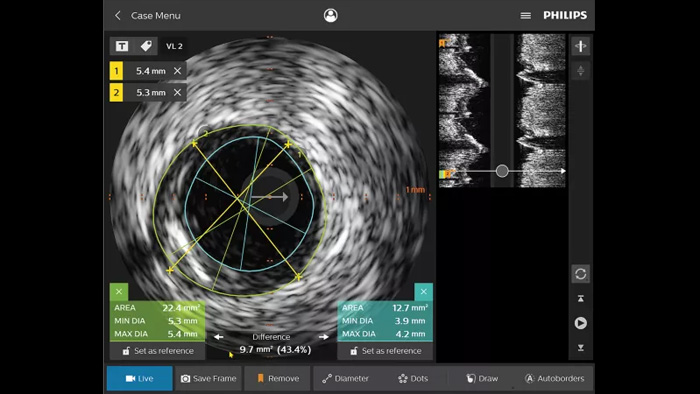

IVUS devices

Intravascular ultrasound (IVUS) is a catheter-based imaging technology that allows physicians to visualize blood vessels from the inside out to aid assessment of presence and extent of disease. IVUS helps to decide, guide and confirm the right interventional treatment for each patient.

IntraSight

IntraSight provides more information through iFR/FFR and IVUS modalities in conjunction with the angiogram - controlled table side on the touch screen. It is built on a foundational platform capable of quickly adding new innovations to your lab.